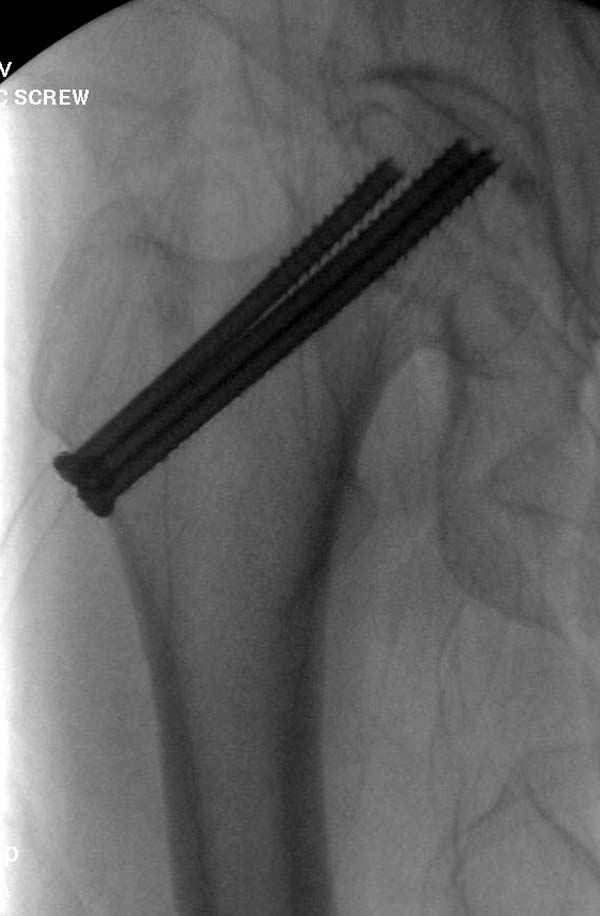

Профилактику дальнейшего раскола неполного перелома шейки провели тремя канюлированными шурупами.

На второй день после выписки упал дома. Снимки приложены. Коллеги рекомендуют удаление шурупа и вытяжение. Что делать?

Привет из солнечного Будапешта с Eurotrauma-2008. Да, замечательный пример. Получается, профилактику расхождения отломков шейки надо было проводить каким-то реконструкционным или проксимальным гвоздем, причем сразу длинной версией. Сейчас, наверно, так и надо бы сделать.

Убрать винты, каким-то джойстиком в вертельной области сделать репозицию шейки, фиксировать ее спицами, а дальше вправлять и фиксировать как вертельный перелом.

Решайте проблемы по мере поступления. На первом этапе решение одно, и на мой взгляд верное. Ситуация изменилась кардинально - другое решение. Я бы избрал ресинтез, убрав винты заменил на Гамму. Что с ним будет послезавтра? - Будем решать послезавтра. Такая наша доля.

Наверное речь идет насчет parallel guide из набора. Применяем по возможности всегда, но,

как видно на снимке, не всегда получается

паралельно.

Такие несмещенные переломы обычно для молодых резидентов, и бывают технические неточности, но в этом случае посчитали фиксацию адекватной.